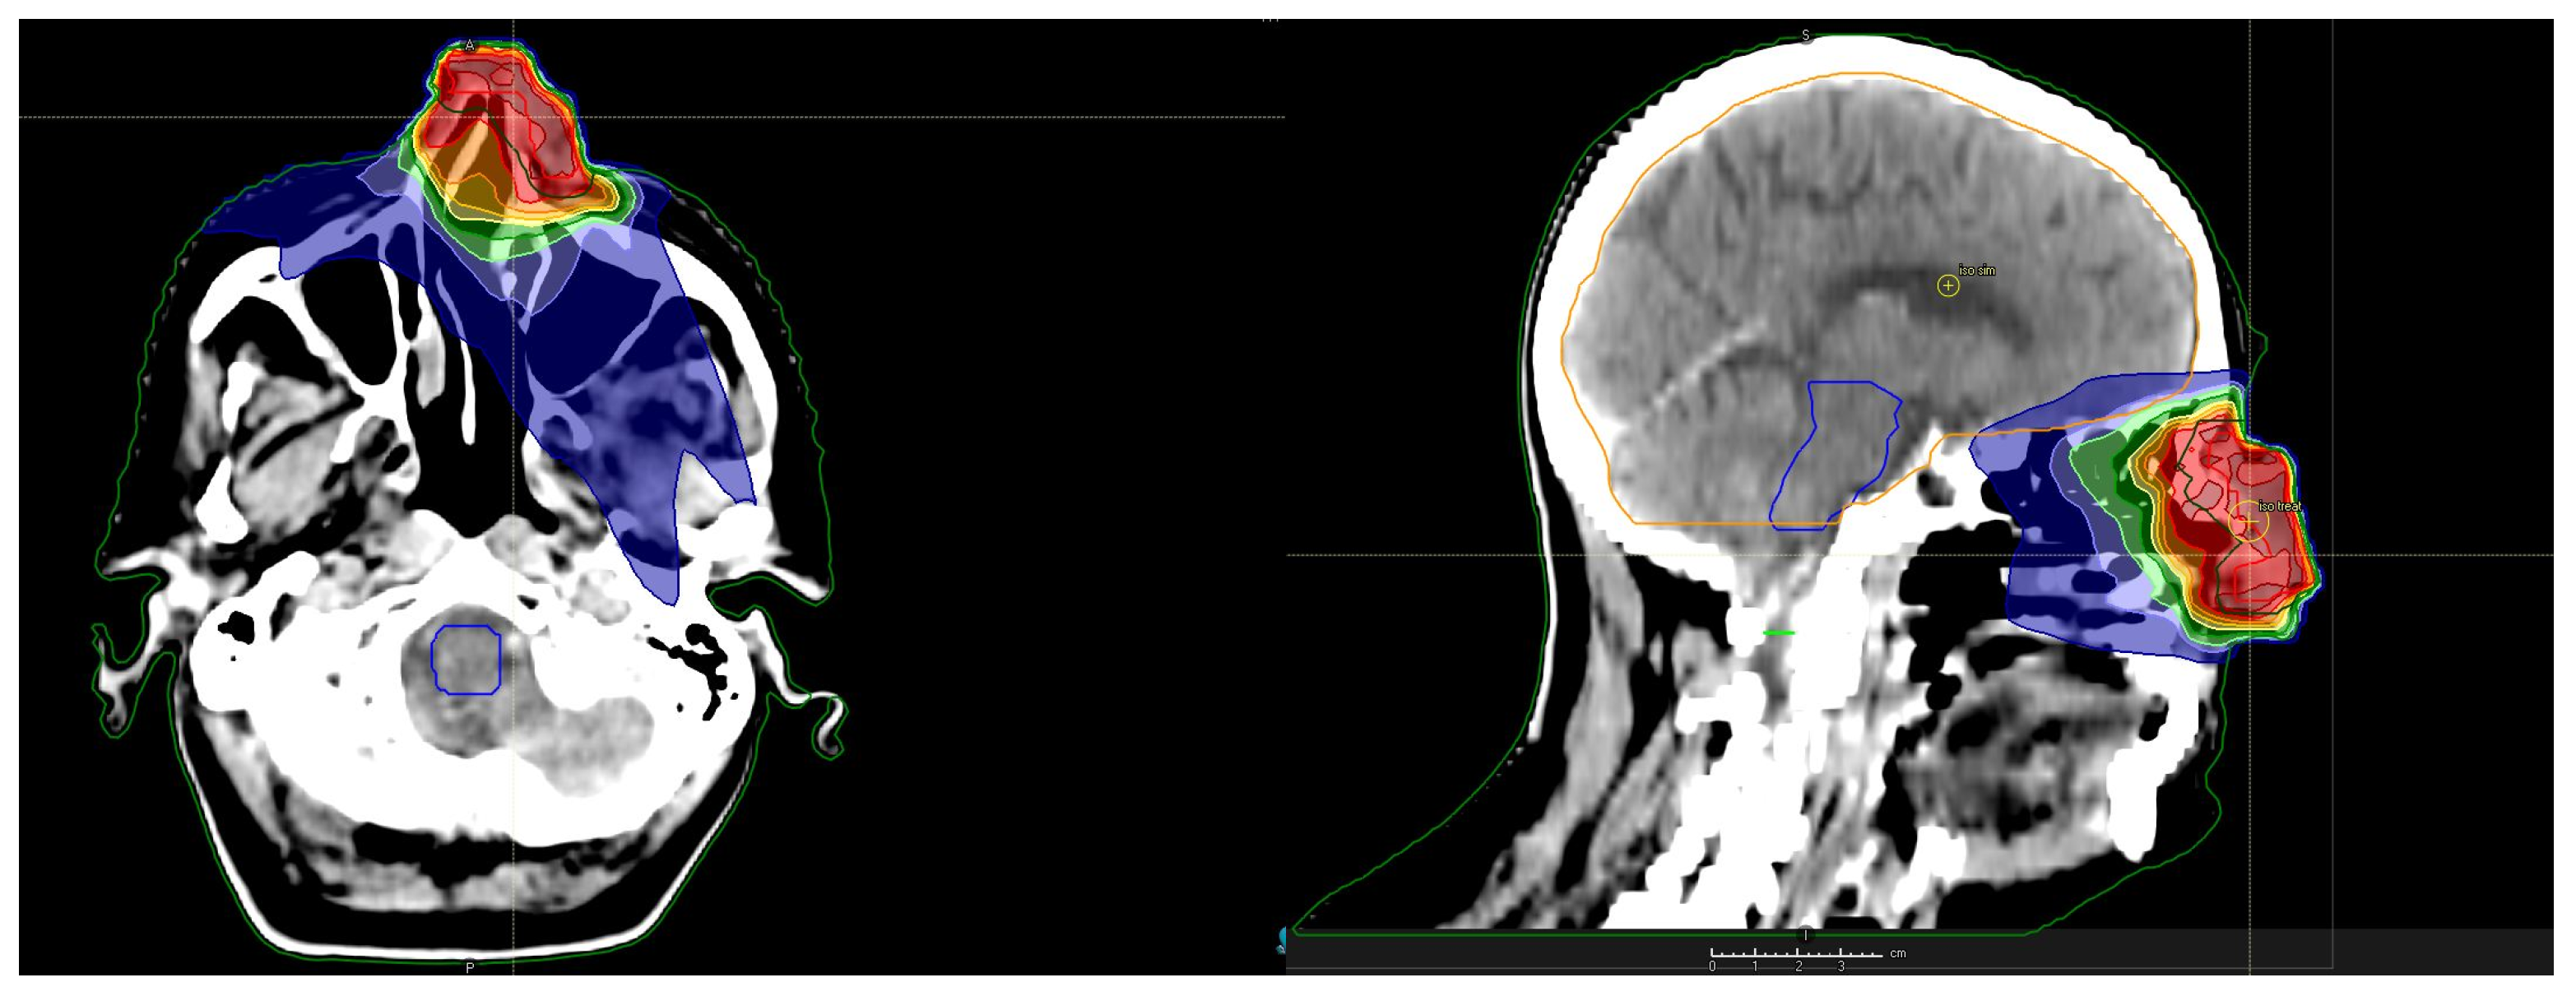

2. Presentation of the Case